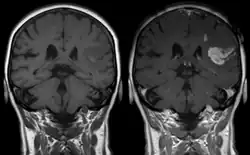

Effet de l'agent de contraste sur les images : défaut de la barrière hémato-encéphalique après un AVC pondéré en T1, image de gauche sans, image de droite avec administration de produit de contraste.

Les chélates de Gd3+ sont hydrophiles et franchissent seulement une barrière hémato-encéphalique compromise, telle que les lésions et les tumeurs.